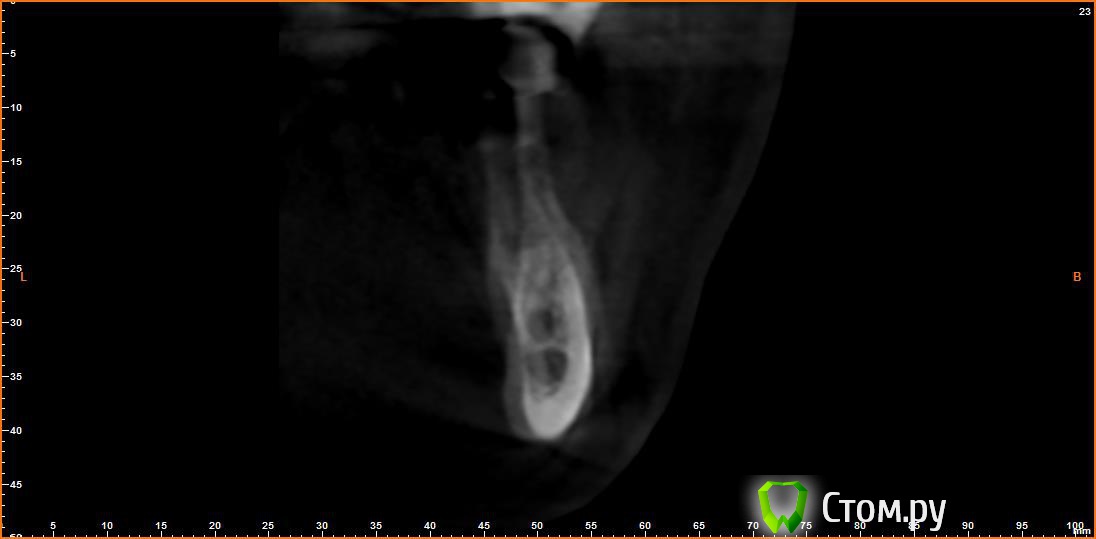

Opimar Опубликовано 21 июня, 2014 Автор Поделиться Опубликовано 21 июня, 2014 Выкладываю еще. Пошагово от 34-37 Ссылка на комментарий

Bier Опубликовано 21 июня, 2014 Поделиться Опубликовано 21 июня, 2014 Выкладываю еще. Пошагово от 34-37темная точка достаточно высоко, это по моему не нерв, нерв ниже, я правильно понимаю? Ссылка на комментарий

Opimar Опубликовано 21 июня, 2014 Автор Поделиться Опубликовано 21 июня, 2014 темная точка достаточно высоко, это по моему не нерв, нерв ниже, я правильно понимаю?Да он ниже и язычнее. Провел от менталиса там еще запас есть. Ссылка на комментарий